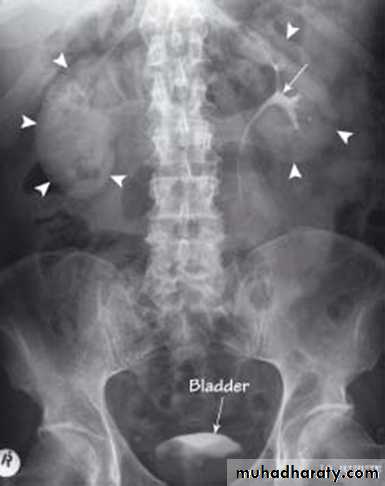

KUB

The IVU series consist of:1-KUB film…To identify any calcification like stones or nephrocalcinosis.

CALCULIMost renal stones are calcified and show varying density on plain x-ray films.

Pure uric acid & xanthine stones are radiolucent on plain radiography, but are well seen at CT or US.

Plain film is more sensitive than US for detecting ureteric calculi.

Stones regardless their composition are intensely echogenic (By U/S) and cast acoustic shadows